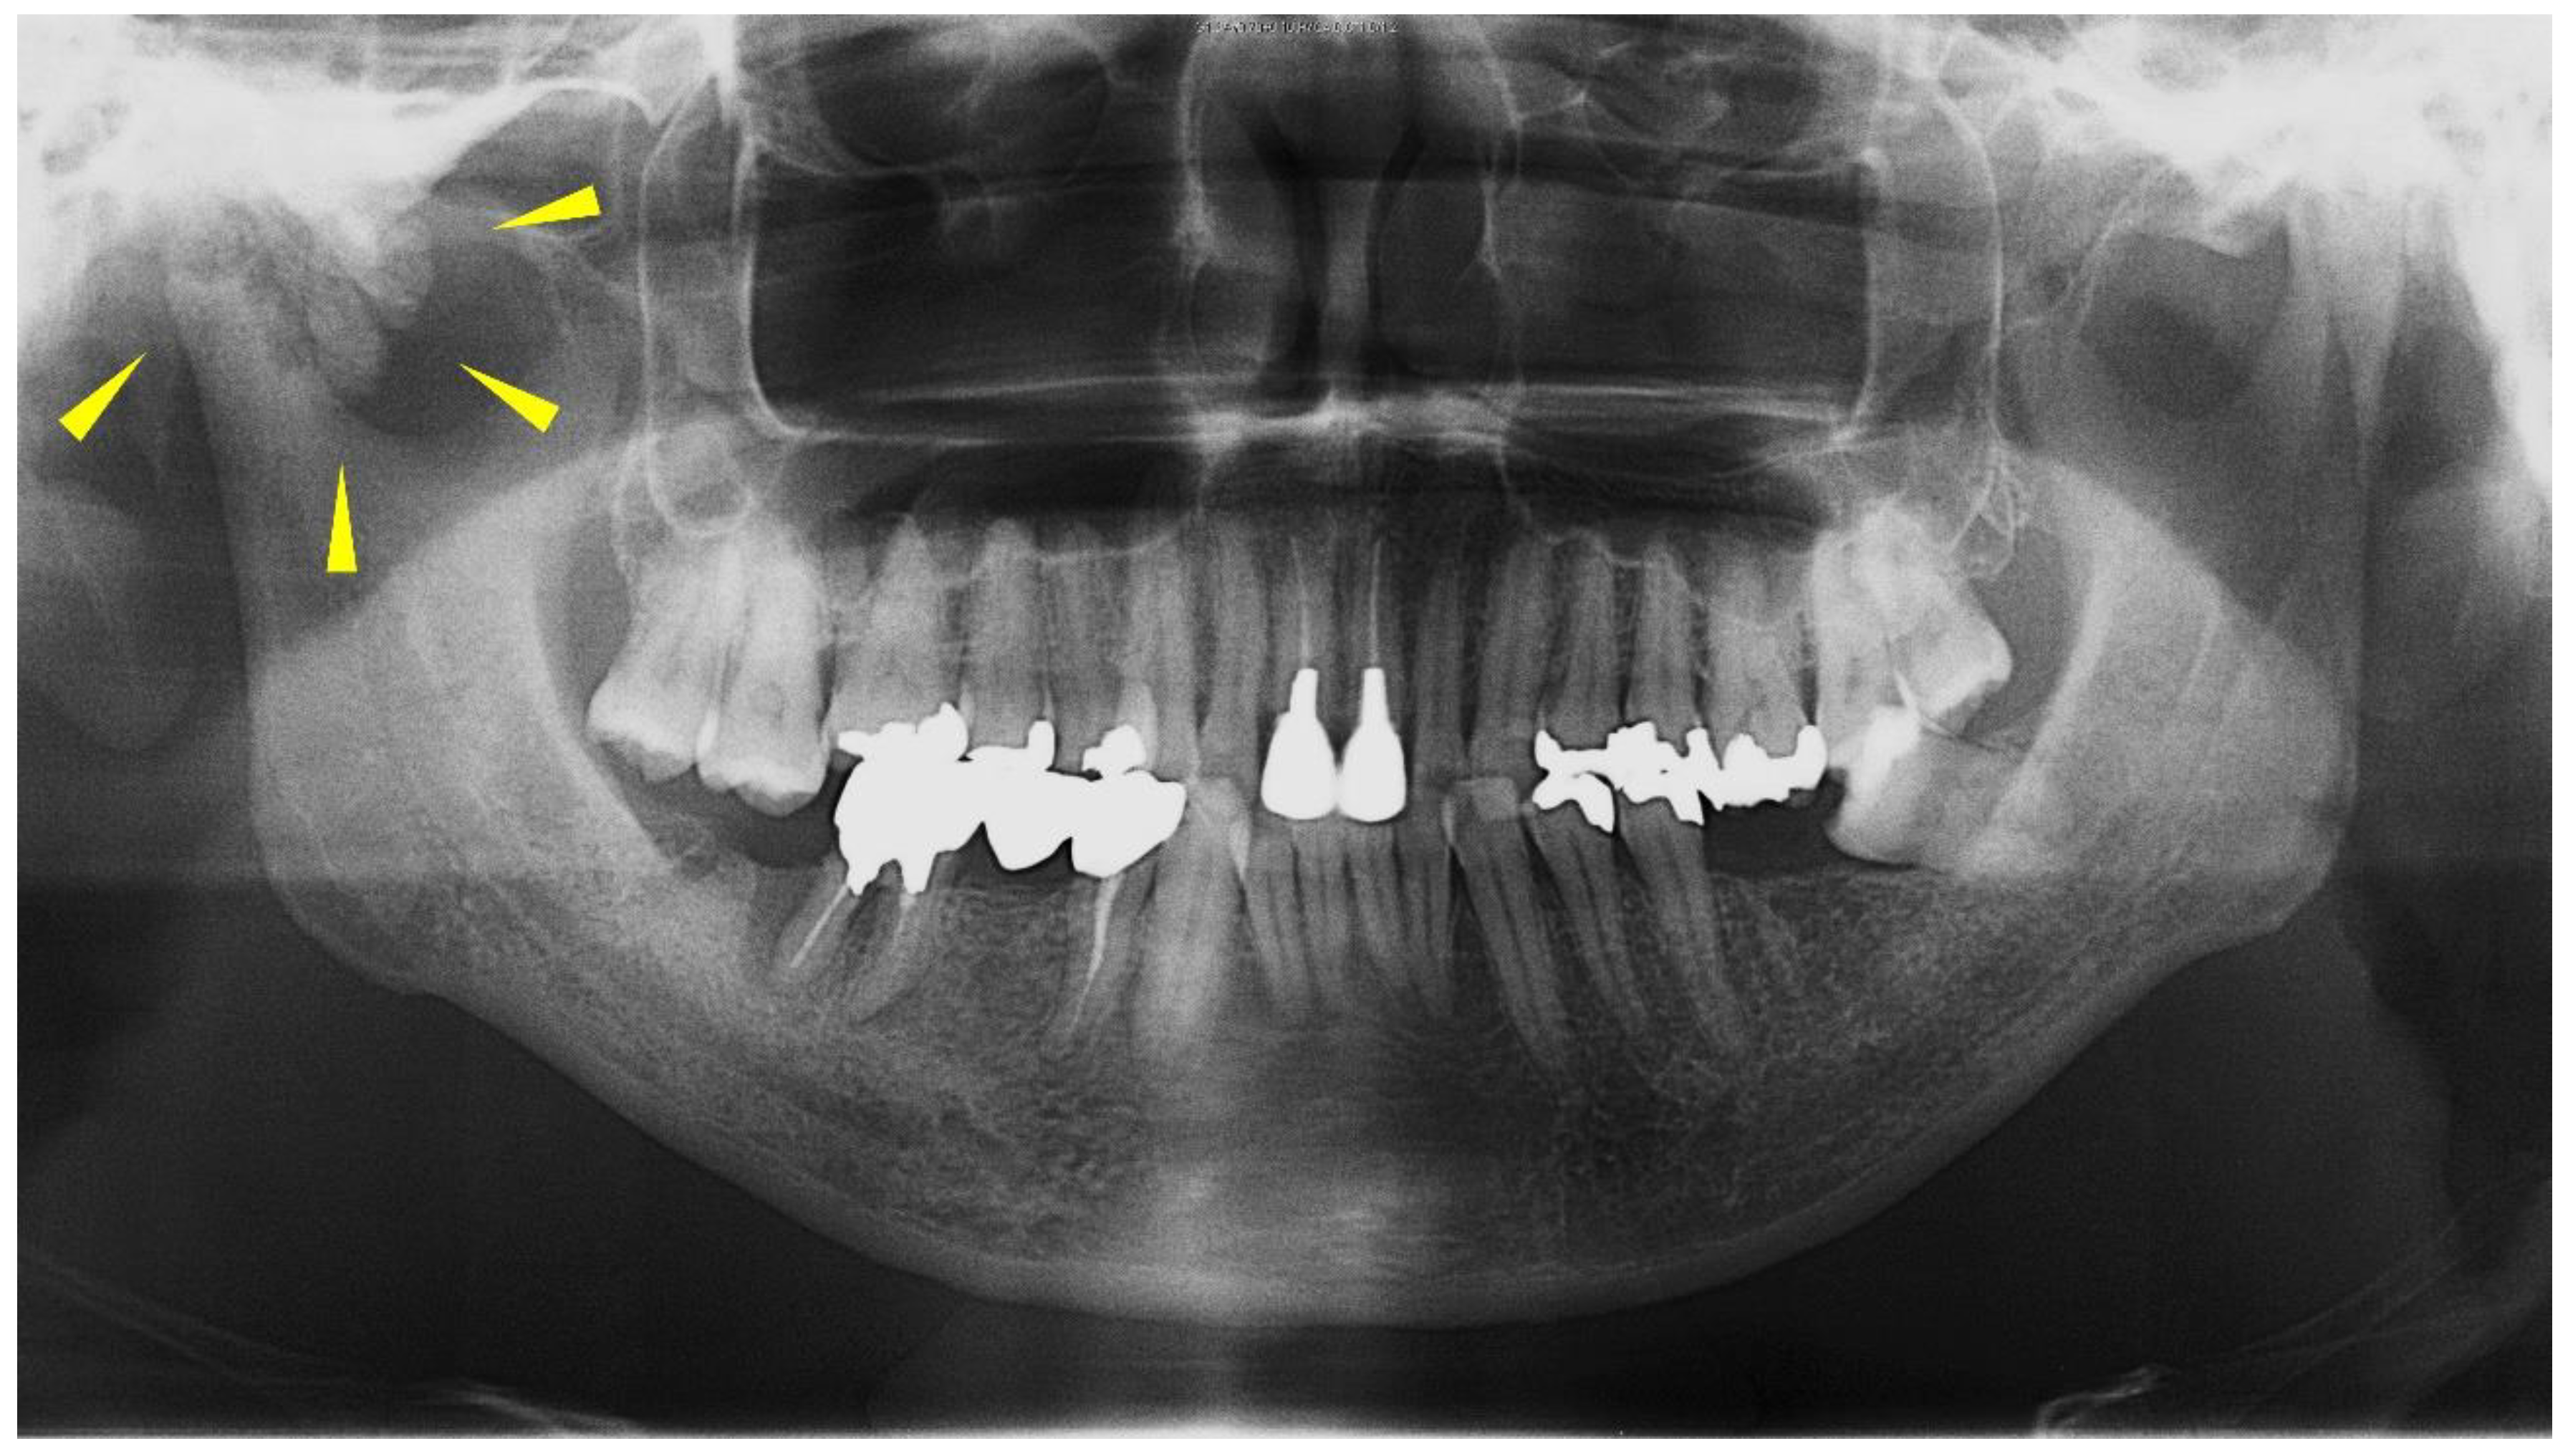

Figure 1.

Panoramic radiograph from the first visit. The ill-defined calcification around the mandibular condyle is shown (yellow arrows).

The panoramic radiograph showed an unclear right mandibular condyle with a cloud-like mass (Figure 1). Computed tomography (CT) revealed that the right mandibular condyle was destroyed, and that mottled-like hard tissues had formed around the condyle as viewed on the axial plane (Figure 2A). Similarly, it was confirmed on the coronal plane that the mandibular fossa and cranial base were destroyed. Furthermore, calcified opacity was observed in the bone resorption fossa (Figure 2B). Proton density-weighted imaging showed no disc dislocation in the right TMJ, and the area corresponding to the upper and lower joint space was filled with uneven hypointensity, and the joint space appeared dilated. Additionally, the high signal inside and granular low-signal images were scattered inside the mandibular condyle and fossa (Figure 3). The left TMJ showed no abnormal findings. Based on these findings, we suspected CPPD deposition disease as a clinical diagnosis and excised the lesion under general anesthesia. The right TMJ was exposed using a preauricular approach. During surgery, we confirmed and removed the white chalk-like masses (Figure 4). These masses were present in the articular capsule, articular eminence, mandibular condyle, the upper and lower joint cavities, and articular disc. The maximum size of the masses was 16 × 5 × 5 mm, although various sizes were extracted. CT images were obtained after surgery, and we confirmed that the masses were extracted from the right temporomandibular joint (Figure 5). The postoperative healing was uneventful. This was six months post-surgery, and although the pain in the right TMJ was persistent when opening the mouth, the maximal mouth opening had improved to 42 mm.